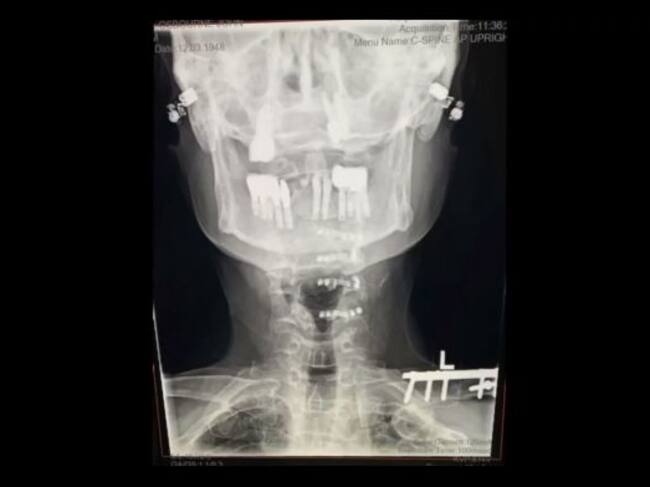

"A principios de año tuve una mala caída y necesité cirugía. Ahora tengo más tuercas y tornillos en el cuello que en mi coche. No me estoy muriendo, me estoy recuperando, es solo que llevará un poco más de tiempo de lo que todos pensaban", ha dicho Osbourne en el vídeo que ha compartido.

Radiografía del cuello de Ozzy Osbourne tras la instalación de prótesis metálicas. / Ozzy Osbourne